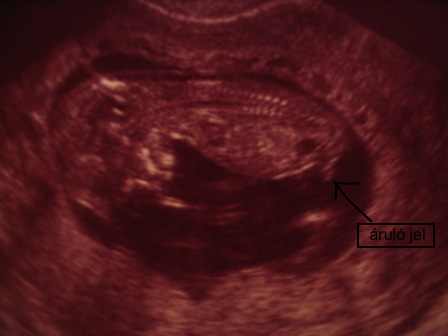

a kért kép:

Kép

Zsófi, de jó, h. feltetted az uh-os felvételt. Ott a jel, nini:)